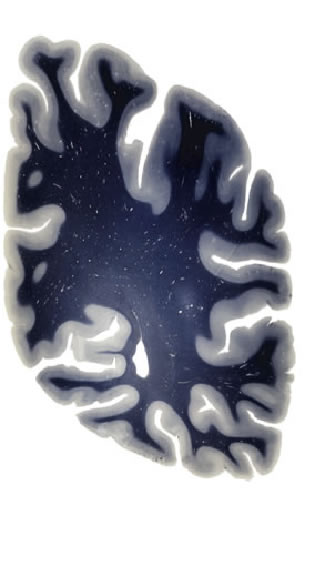

Hi-Resolution Sections · Cells (Nissl Staining) · Virtual Microscopy

Frontal sections (Nissl) from the Atlas Brain:

Slice ID:

r4-0620

Plate NR:

56

Position:

53,5 mm